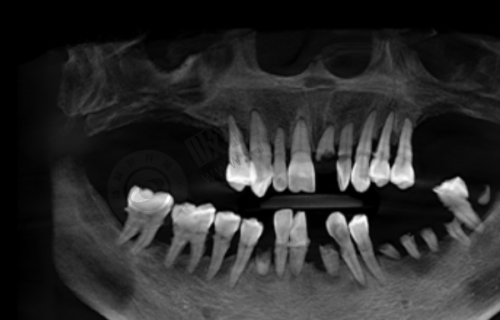

陕西省人民医院口腔科可开展全口数字化种植、ONLY 植骨术、骨劈开术、GBR 手术、即刻种植、上颌窦外提升等高难度的种植技术。

西安交通大学医学校第一附属医院口腔科引入机器人种植(5 分钟/颗)、3D 导板设计,减少人力与耗材浪费;提供3D 数字化模拟矫正方案,提前预览牙齿移动轨迹。